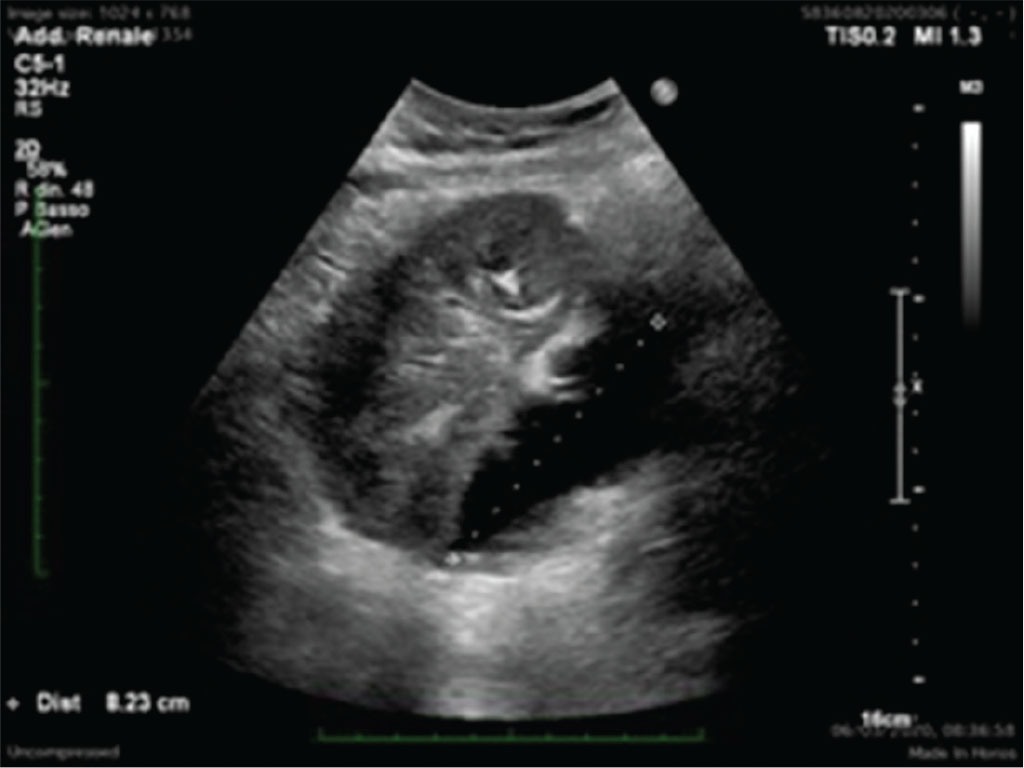

Qualsiasi tipo di nefropatia, sia essa primariamente parenchimale, vascolare o urologica, in fase terminale determina il fallimento del TR. Il trapianto renale non funzionante solitamente viene lasciato in situ. L’ERT è importante anche una volta che il trapianto è fallito. È essenziale praticare un monitoraggio stretto delle caratteristiche ecografiche del TR nel corso della progressiva riduzione della terapia immunosoppressiva e, ancora, nel follow-up a lungo termine. Rigetti acuti possono manifestarsi e possono rendersi particolarmente pericolosi anche per la vita del paziente, così come, nel lungo temine, lesioni neoplastiche possono svilupparsi sul rene trapiantato ormai non più funzionante. Dal punto di vista ecografico, il rene trapiantato cronico e non funzionante non ha caratteristiche dissimili da quelle di un rene nativo non funzionante: infatti, le dimensioni si riducono progressivamente, viene completamente alterata la differenziazione cortico-midollare e si osserva una globale riduzione della vascolarizzazione intraparenchimale. Spesso si possono presentare degenerazioni cistiche anche particolarmente estese (soprattutto dopo molto tempo dalla ripresa della terapia sostitutiva) e il parenchima può essere sede anche di calcificazioni estese (Fig. 3).

(Personal image, Fondazione IRCCS Ca’ Granda Ospedale Maggiore Policlinico, Milano)